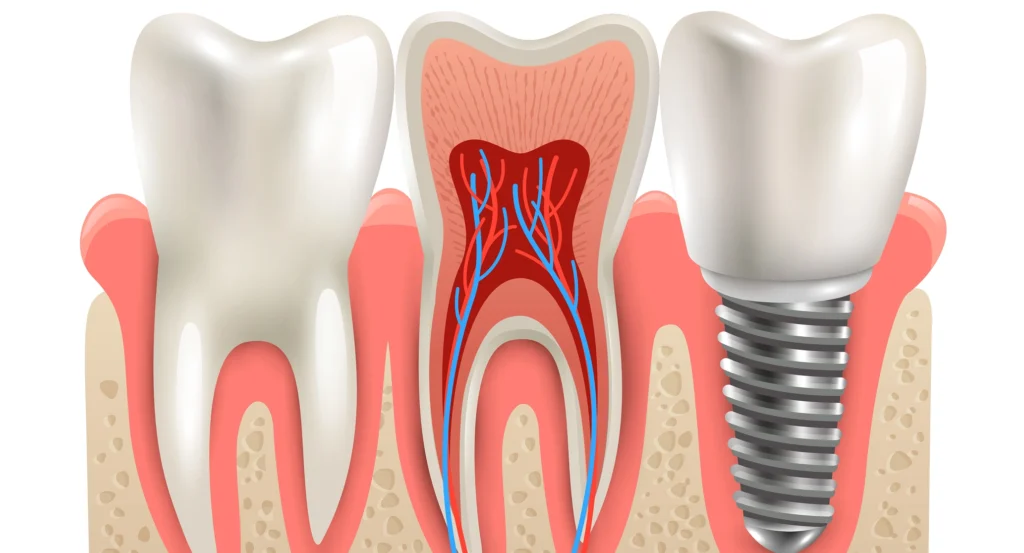

A dental implant acts like an artificial tooth root. It sits in the bone and supports a crown, bridge or full‑arch set of teeth. The quality of the planning decides how comfortable and long‑lasting the result will be.

Implants help maintain bone volume and facial structure, especially when placed soon after tooth loss. They do not depend on neighbouring teeth for support, so we don’t have to grind down healthy teeth the way we do for conventional bridges.